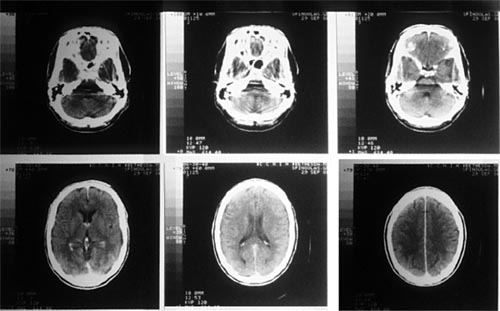

CT掃描儀用X射線作為掃描光線,跟傳統(tǒng)的X光掃描不同的是CT掃描儀不只是拍攝一張圖片,而是會拍攝不同截面的多張圖片,之通過系統(tǒng)將拍攝的圖片合成完整的三維圖像,恢復(fù)被掃描的內(nèi)部結(jié)構(gòu)。

傳統(tǒng)X射線最大的局限在于,傳統(tǒng)的X射線只能提供二維的圖片,因此無法提供器官或身體其他部位內(nèi)部結(jié)構(gòu)的具體信息,真實反映出檢測部位的三維結(jié)構(gòu)。此外,人體許多不同的組織對X射線有相近的吸收能力,導(dǎo)致無法通過X射線區(qū)分這些不同的組織。并且在傳統(tǒng)的X射線檢測中,會有大量的射線被散射掉,導(dǎo)致圖像很不完整。而CT掃描不僅可以提供被檢測部位內(nèi)部結(jié)構(gòu)的三維圖像,還可以區(qū)分不同的組織,并將X射線集中在特定的檢測區(qū)域,從而得到更清晰的圖像。